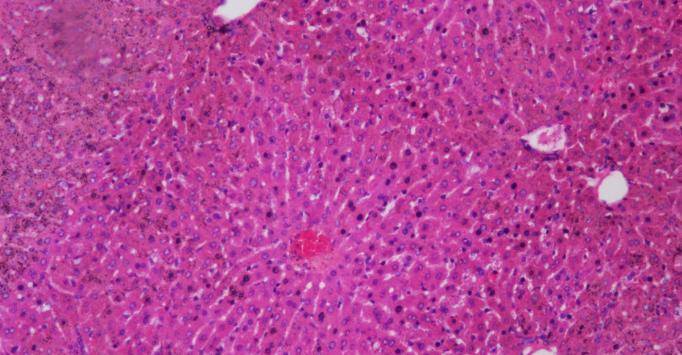

长期高强度饮酒,肝细胞反复受损,慢慢就会累积成问题。肝脏的损伤往往是慢慢积累,不是“喝一回就出事”。所以,酒量和肝脏健康之间,并没有直接的等号。

肝脏是个“哑巴工人”,能忍能扛,但不是没底线。肝脏损伤早期几乎没明显症状,等到身体出问题,往往已经积重难返。